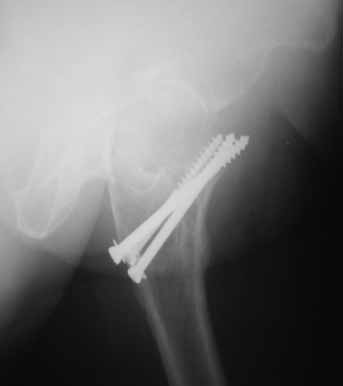

На консультации вот такие снимки. Больная 72 года. упала в быту 26 декабря 2010г.

Оперирована 30 декабря 2010г. в одном из стационаров края. Назначили дополнительное обследование, а пока хотелось-бы услышать мнение по-поводу возможностей сохранения головки. Больная из льготного контингента, т.е. современные констукции и эндопротез маловероятны.

Обычное после фиксации перелома шейки варусное смещение по разным публикациям встречается от 15-24%. В оценке состояния пожилых больных применяется коэффициент (ADL) Activities of daily living. В зависимости от базового ADL, т.е. до переломного состояния планируется лечение. Кроме того, возраст играет важную роль, и не всегда функциональное состояние совпадает с истинным возрастом. Поэтому каждый случай после 60 лет рассматривается отдельно.

Показанием к органосохраняющей вальгусной остеотомии является более молодой возраст. Более пожилым, тем более в 72 г., можно ограничиться дешевым цементным эндогемипротезом. Биполярные эндопротезы приводят к удорожанию операции, и нет данных, что они функционируют лучше. Компоненты головки замыкаются друг в друге после первых вращений, и действует как одно целое.